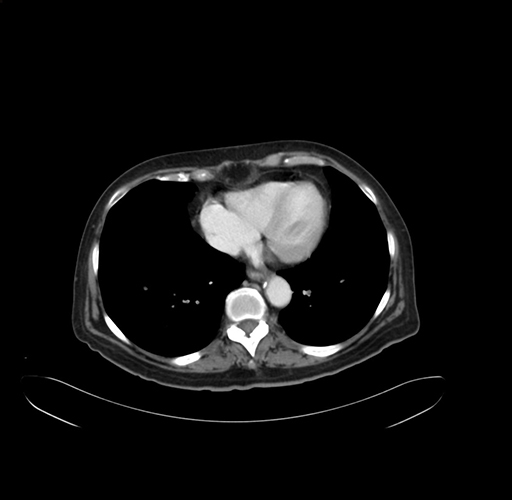

Pre-Chemo: Axial Venous

Axial Venous